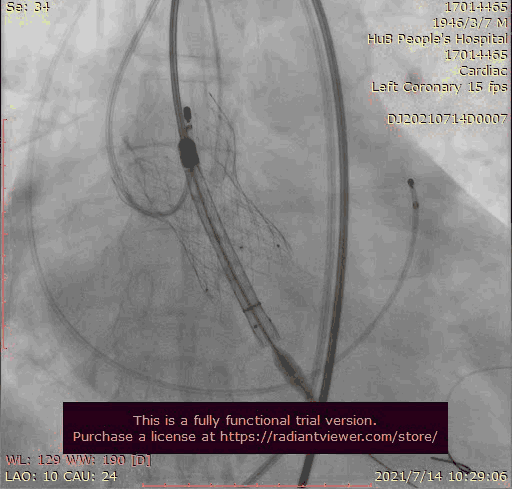

瓣膜稍高位释放

瓣膜位置稍深

使用venus-A plus回收后重新定位释放

1.在第一次释放瓣膜时,由于患者主动脉根部瓣上瓣下均比瓣环平面大,受到血流的冲击,瓣膜滑至较深的位置,使用venus-A PLUS回收

2.回收后重新定位释放,由于第一次滑至较深,第二次稍微卸力后瓣膜跳至窦上,使用venus-A PLUS回收,再次重新定位